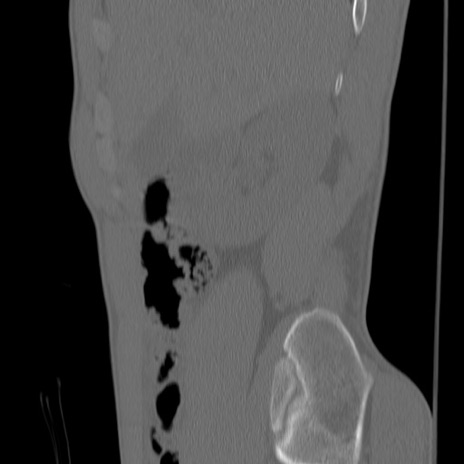

症例3 腰椎CT(矢状断像)

【症例】30歳代男性

【主訴】腰痛

【現病歴】本日旅行先で観光中に、友人と衝突し転倒し受傷。

【身体所見】麻痺なし、右下腿内側前面外側、左下腿内側に知覚鈍麻・しびれ

異常所見と診断は?

腰椎CT